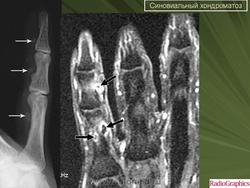

Синовиальный хондроматоз

http://radiographics.rsna.org/content/27/5/1465.full